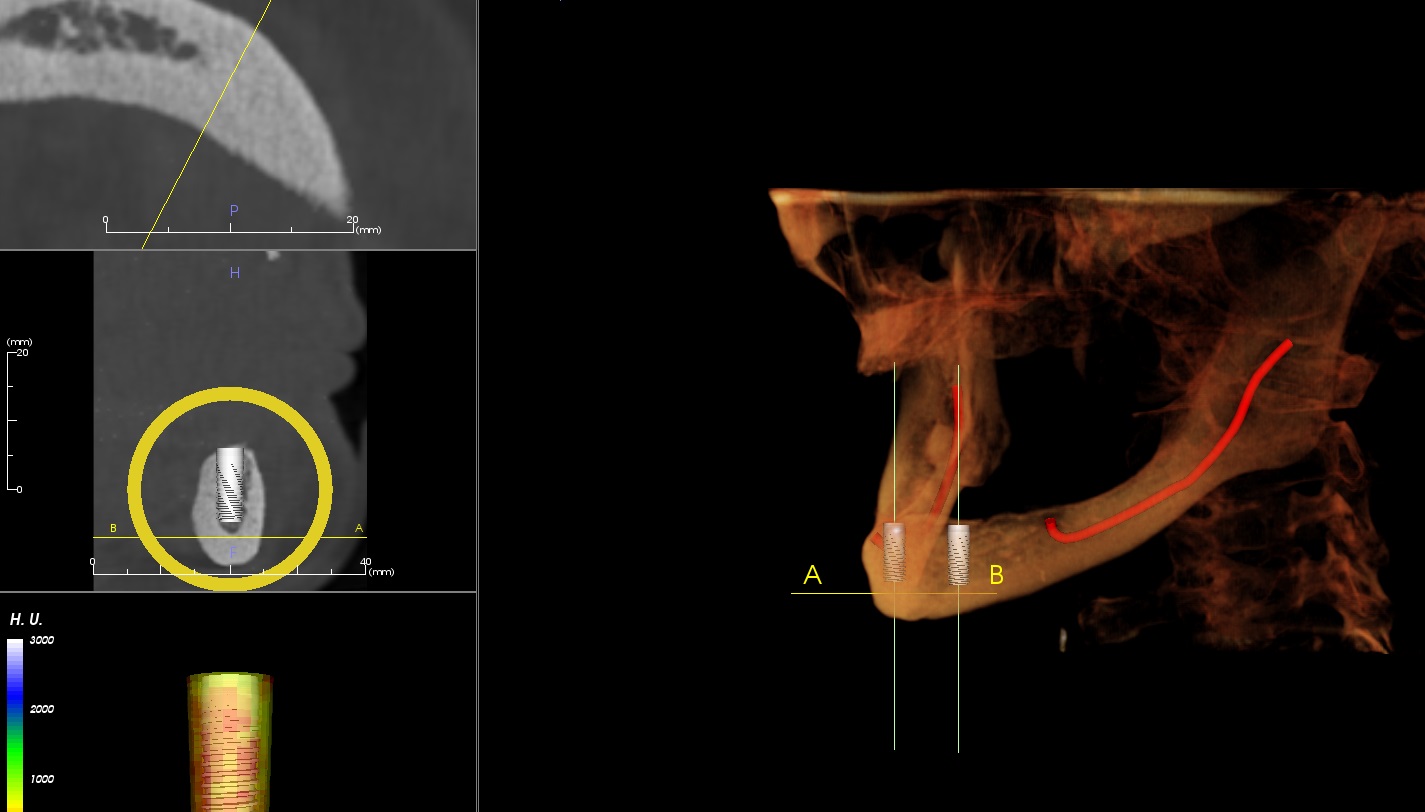

Most patients are candidates for dental implants. Our process starts with a 3-D CT Scan where we will take a look at the jaws and see the available bone and design your dental implant treatment plan before your eyes. Dr. Damon or Dr. Whittington will discuss the different treatment options as well as the different benefits the plans provide.